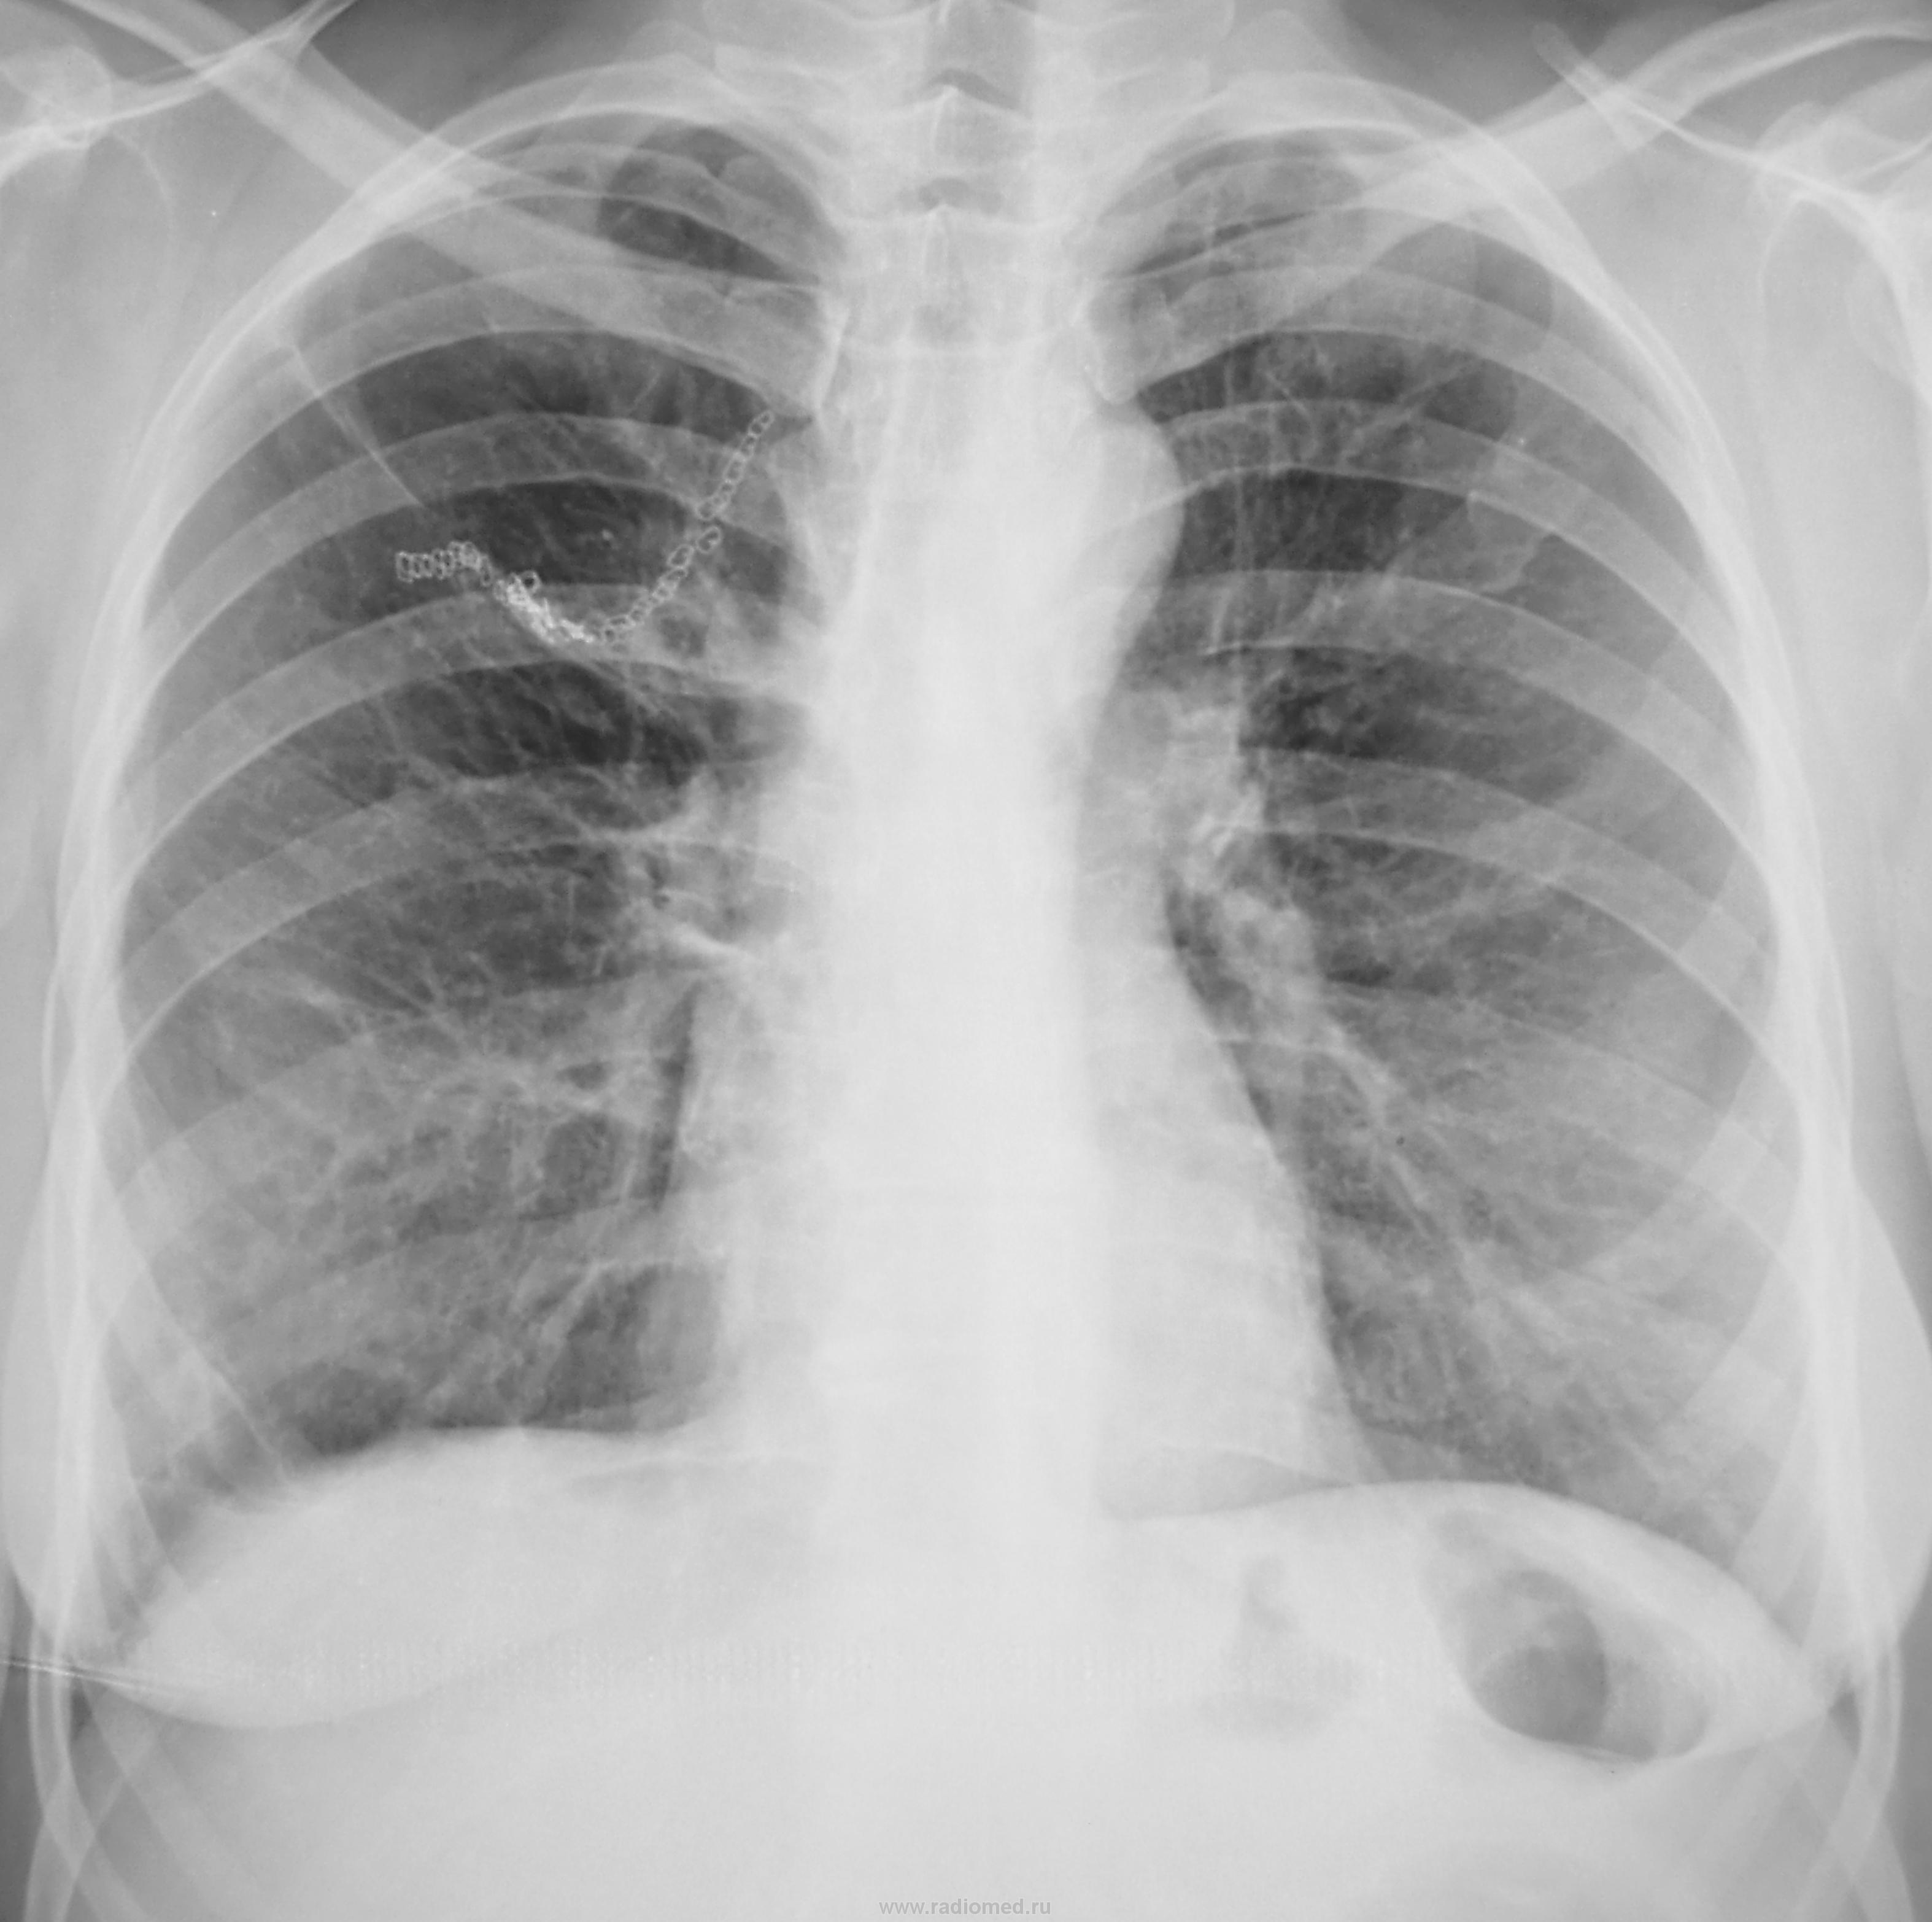

Пол пациента: Женский пол Тип патологии: Другое Область исследования: Грудная клетка и верхние дыхательные пути Методы исследования: Rg Какие мнения будут по снимку? https://radiomed.ru/sites/default/files/styles/case_slider_image/public/user/12/12.dscn0592a.jpg?itok=BSdOZYlK ID:24532 Чт, 15/11/2012 - 18:44 #1 Андрей Багаев Не на сайте Был на сайте: 11 лет 2 месяцев назад Зарегистрирован: 28.01.2011 - 19:14 Публикации: 57 оеперированное правое легкое. что с рисунком-фиброзная деформация? Чт, 15/11/2012 - 19:23 #2 Петр Николаевич Не на сайте Был на сайте: 3 года 10 месяцев назад Зарегистрирован: 15.03.2011 - 13:22 Публикации: 150 Андрей Багаев wrote: оеперированное правое легкое. что с рисунком-фиброзная деформация? танталовые швы, скорее всего оперативное вмешательство по поводу туберкулеза (удаление туберкулемы, каверны). Пт, 16/11/2012 - 12:42 #3 RuslanChupanov Не на сайте Был на сайте: 3 года 11 месяцев назад Зарегистрирован: 23.08.2011 - 13:01 Публикации: 31 Глаз цепляется за верхушку левого легкого, мерещится округлое образование...Приложения: Пт, 16/11/2012 - 13:24 #4 Nikolas Не на сайте Был на сайте: 2 месяцев 1 неделя назад Зарегистрирован: 21.12.2010 - 20:37 Публикации: 4559 RuslanChupanov. Сб, 17/11/2012 - 11:13 #5 Гаврилов Кирилл... Не на сайте Был на сайте: 7 лет 10 месяцев назад Зарегистрирован: 03.11.2009 - 21:50 Публикации: 87 RuslanChupanov wrote: Глаз цепляется за верхушку левого легкого, мерещится округлое образование... Да, что-то есть. Нужно томографить. Рентгеновы лучи никогда не ошибаются. Ошибаемся мы, переводя их на свой язык

оеперированное правое легкое. что с рисунком-фиброзная деформация?

танталовые швы, скорее всего оперативное вмешательство по поводу туберкулеза (удаление туберкулемы, каверны).

Глаз цепляется за верхушку левого легкого, мерещится округлое образование...

Да, что-то есть. Нужно томографить.